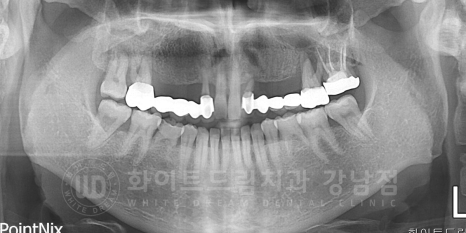

환자분의 x-ray 사진을 확인해 보겠습니다.

12 x 16번, 22 x 26번 치아가 각각 5unit 브릿지로 연결이 되어있습니다.

강남역 치과브릿지 / 치료 전 X-RAY

환자분의 x-ray를 보면 뿌리가 유난히 짧은 치아가 2개 있습니다.

성인이 유치가 남아있다고?

이렇게 생각하실 수도 있는데, 선천적으로 영구치가 나오지 않아 성인이 된 후에도

유치가 남아있는 경우들이 종종 있답니다.

유치는 영구치에 비해 치아 뿌리가 짧기 때문에 강한 힘을 받으면 흔들리거나 손상될 확률이 큽니다.